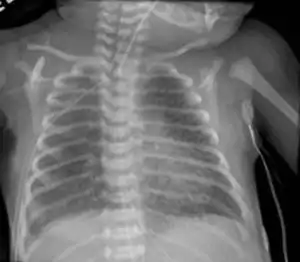

Infant respiratory distress syndrome most commonly occurs in less than six hours after birth in about 1% of all births in the United States.[9] The main risk factor is prematurity with the likelihood of it occurring going up to 71% in infants under 750g.[19] Other risk factors include infant of a diabetic mother (IDM), method of delivery, fetal asphyxia, genetics, prolonged rupture of membranes (PROM), maternal toxemia, chorioamnionitis, and male sex. The widely accepted pathophysiology of respiratory distress syndrome is it caused by insufficient surfactant production and immature lung and vascular development. The lack of surfactant makes the lungs atelectatic causing a ventilation to perfusion mismatch, lowered compliance, and increased air resistance. This causes hypoxia and respiratory acidosis which can lead to pulmonary hypertension. It has a ground glass appearance on an x-ray. Symptoms can include tachypnea, nasal flaring, paradoxical chest movement, grunting, and subcostal retractions.[9]